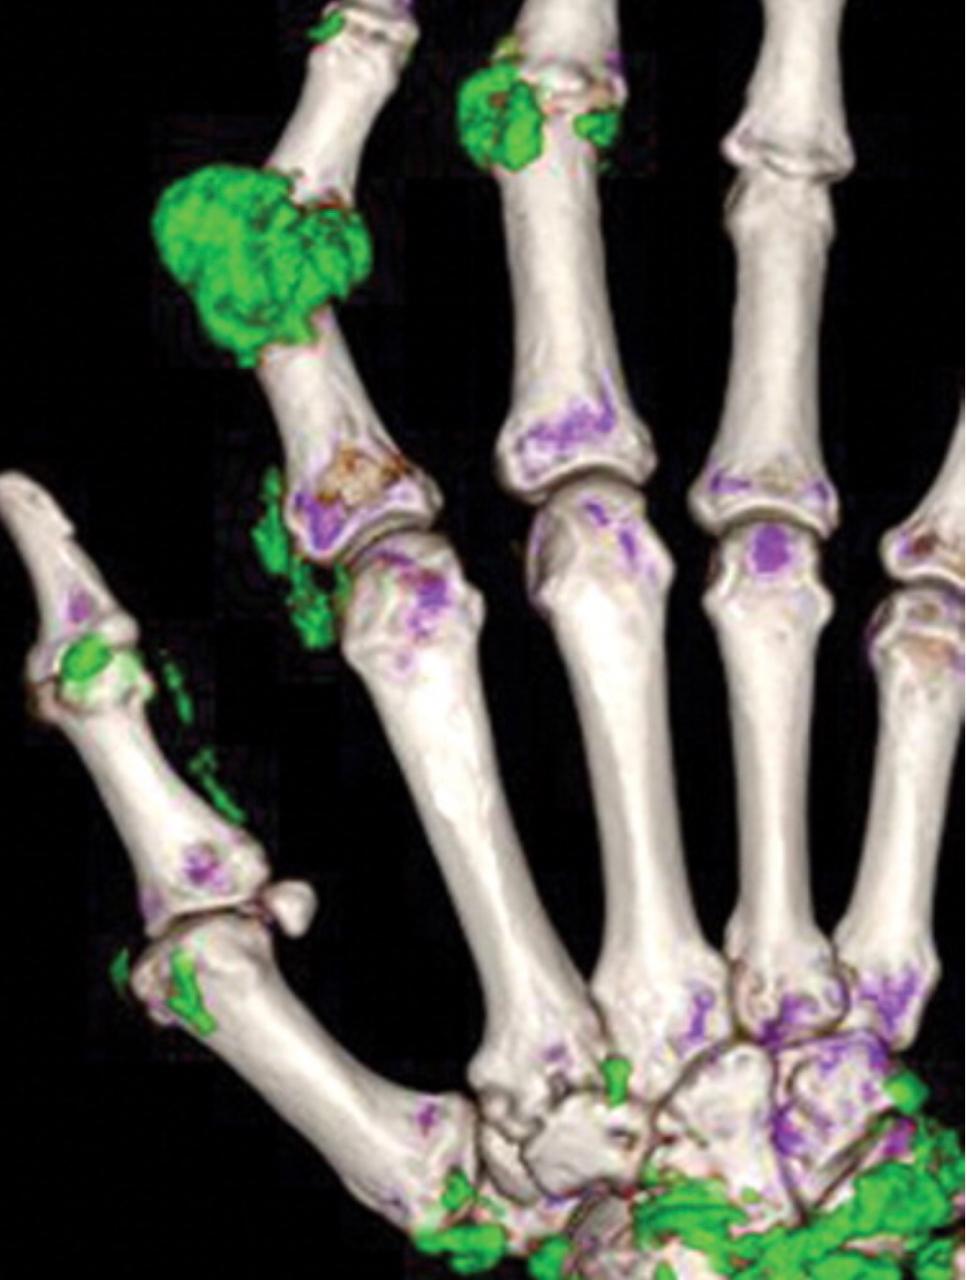

Although diagnosing gout generally is straightforward, atypical disease may present a challenge if it is associated with unusual symptoms or sites, discordant serum urate level, or mimics of gout. Dual-energy computed tomography (CT) may be used to differentiate urate crystals from calcium by using specific attenuation characteristics, which may help diagnose gout. In patients with known tophaceous gout, dual-energy CT may be used for serial volumetric quantification of subclinical tophi to evaluate response to treatment.

Dual-energy CT can quantitatively identify monosodium urate crystal deposits with high sensitivity and specificity within joints, tendons, and periarticular soft tissues.

Given the utility of dual-energy CT in challenging cases and its ability to provide an objective outcomes measure in patients with tophaceous gout, dual-energy CT promises to be a unique and clinically relevant modality in the diagnosis and management of gout.